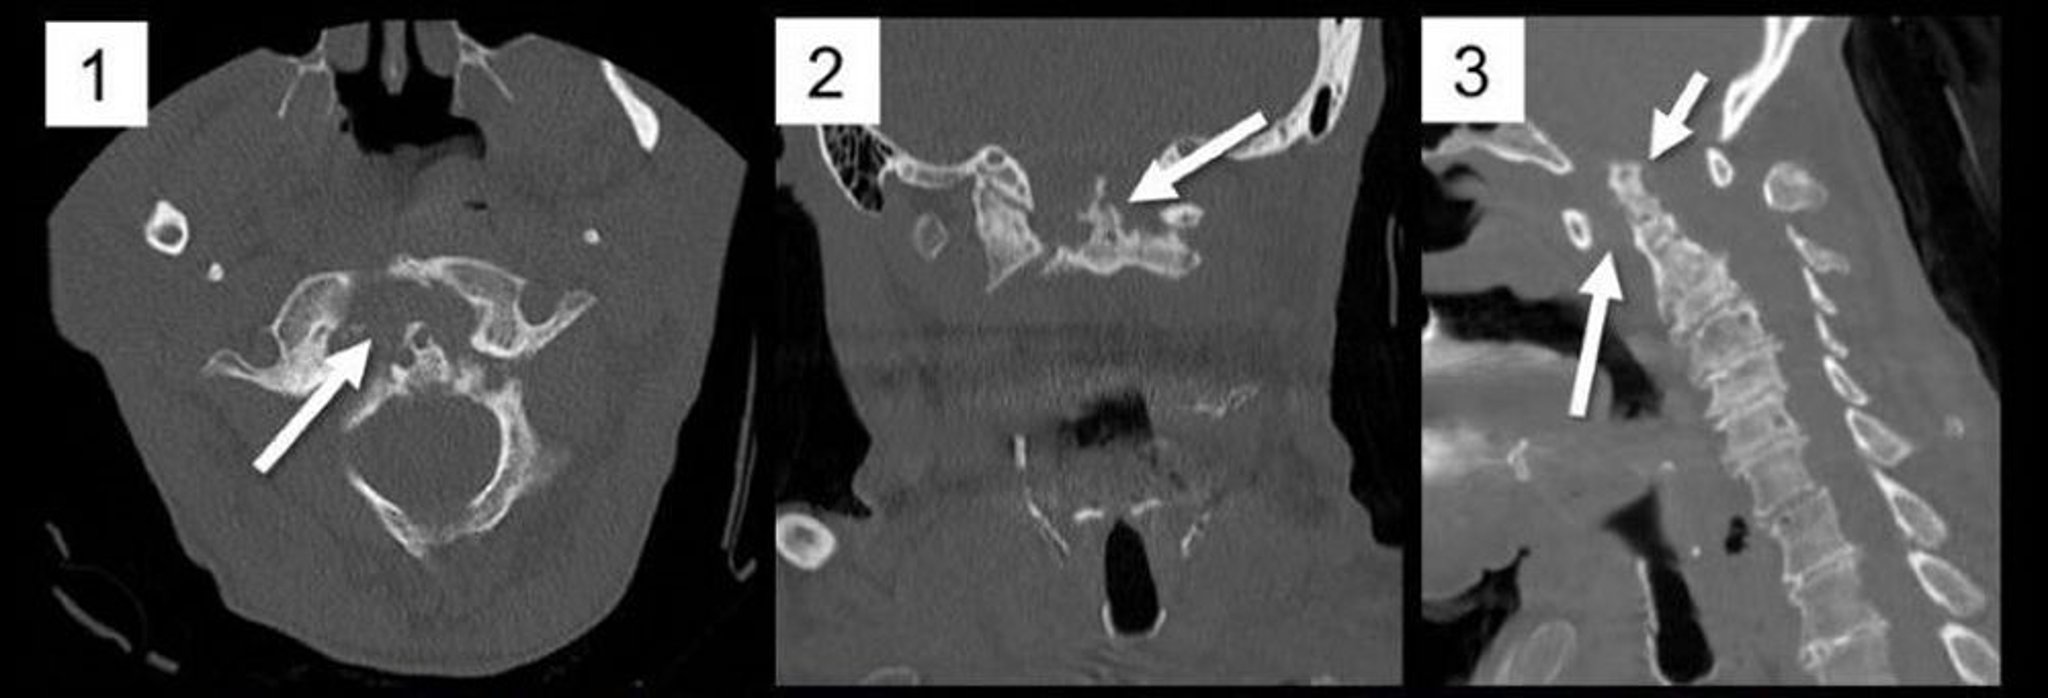

Атлантоаксиальный подвывих (КТ)

На многоплоскостных реформациях компьютерной томографии шейного отдела позвоночника в осевой (1), фронтальной (2) и сагиттальной (3) плоскостях наблюдается заметное расширение переднего атлантодентального промежутка (АДП), вследствие образования паннуса, что происходит при ревматоидном артрите (РА) (1, стрелка; 3, длинная стрелка), вызывая задний подвывих и платибазию от зубовидного отростка C2 (3, короткая стрелка). Зубовидный отросток заметно эрозирован (2, стрелка), типичная находка при РА.

Image courtesy of A. John Tsiouris, MD.